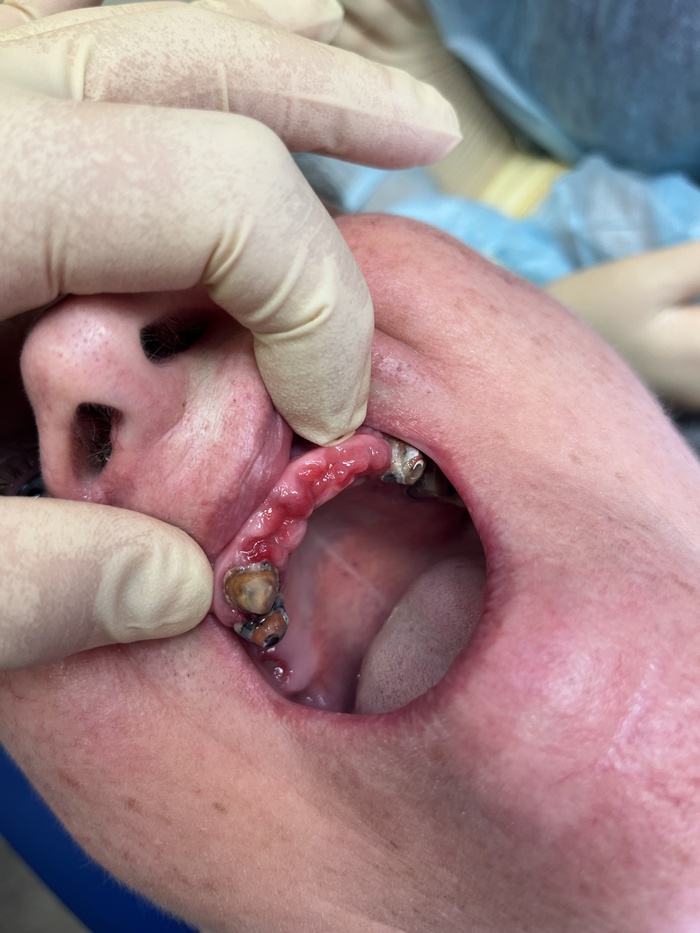

Сняли мы с пациенткой верхний протез с подобным «седлом». Вот, что уже 15 лет живет под ним. Вычистить все это нереально при всем желании даже у врача в кресле.

А вот так выглядит десна под ним